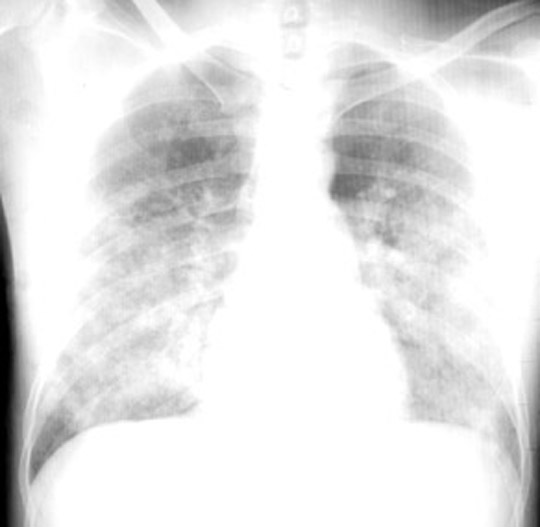

CXR

Path/PE and Pulmonary edema.: Note frothy fluid exuding from lungs.  Dr Ralph Leischner